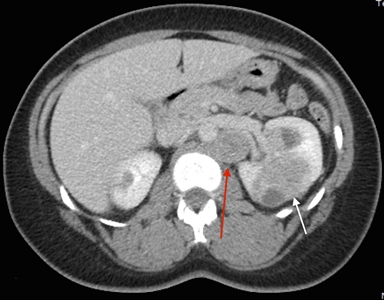

The symptoms of RCC may include hematuria, lower back pain, and a palpable mass. However, a large number of individuals with RCC are asymptomatic. Furthermore, not all individuals with HLRCC present with or develop RCC. Most RCCs are unilateral and solitary; in a few individuals, they are multifocal. The exact incidence of RCC in affected individuals remains to be determined, and widely varying estimates have been provided by different groups (1%–60%).[1,3,8] The incidence appears to vary on the basis of where the study was performed, the referral patterns of individual groups, and the extent to which individuals were screened for RCC. In studies from the National Cancer Institute (NCI), RCC was identified in approximately 32% of families evaluated.[1,3] The median age at detection of RCC was 37 years,[9] although some cases have been reported to occur as early as age 10 years.[10] Another large series of 135 patients estimated that the lifetime risk was 20.8% by age 85 years.[11] In contrast to other hereditary RCC syndromes, RCCs associated with HLRCC are aggressive,[12,13] with a Fuhrman nuclear grade of 3 or 4 in many cases and 9 of 13 individuals dying from metastatic disease within 5 years of diagnosis.[3]Figure 1 depicts RCCs in a patient with HLRCC.

Axial view of an individual's midsection showing tumors in both kidneys. The left kidney has a small tumor and the right kidney has a larger tumor. A retroperitoneal lymph node is shown beside the larger tumor.

Figure 1. Hereditary leiomyomatosis and renal cell cancer–associated renal tumors are commonly unilateral and solitary; in a few individuals, they are multifocal. Red arrow indicates a retroperitoneal lymph node. White arrow indicates a left renal mass.